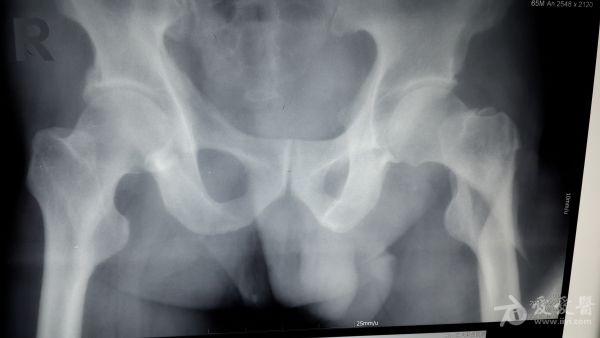

股骨粗隆间粉碎特性骨折的手术方案

男性,65岁